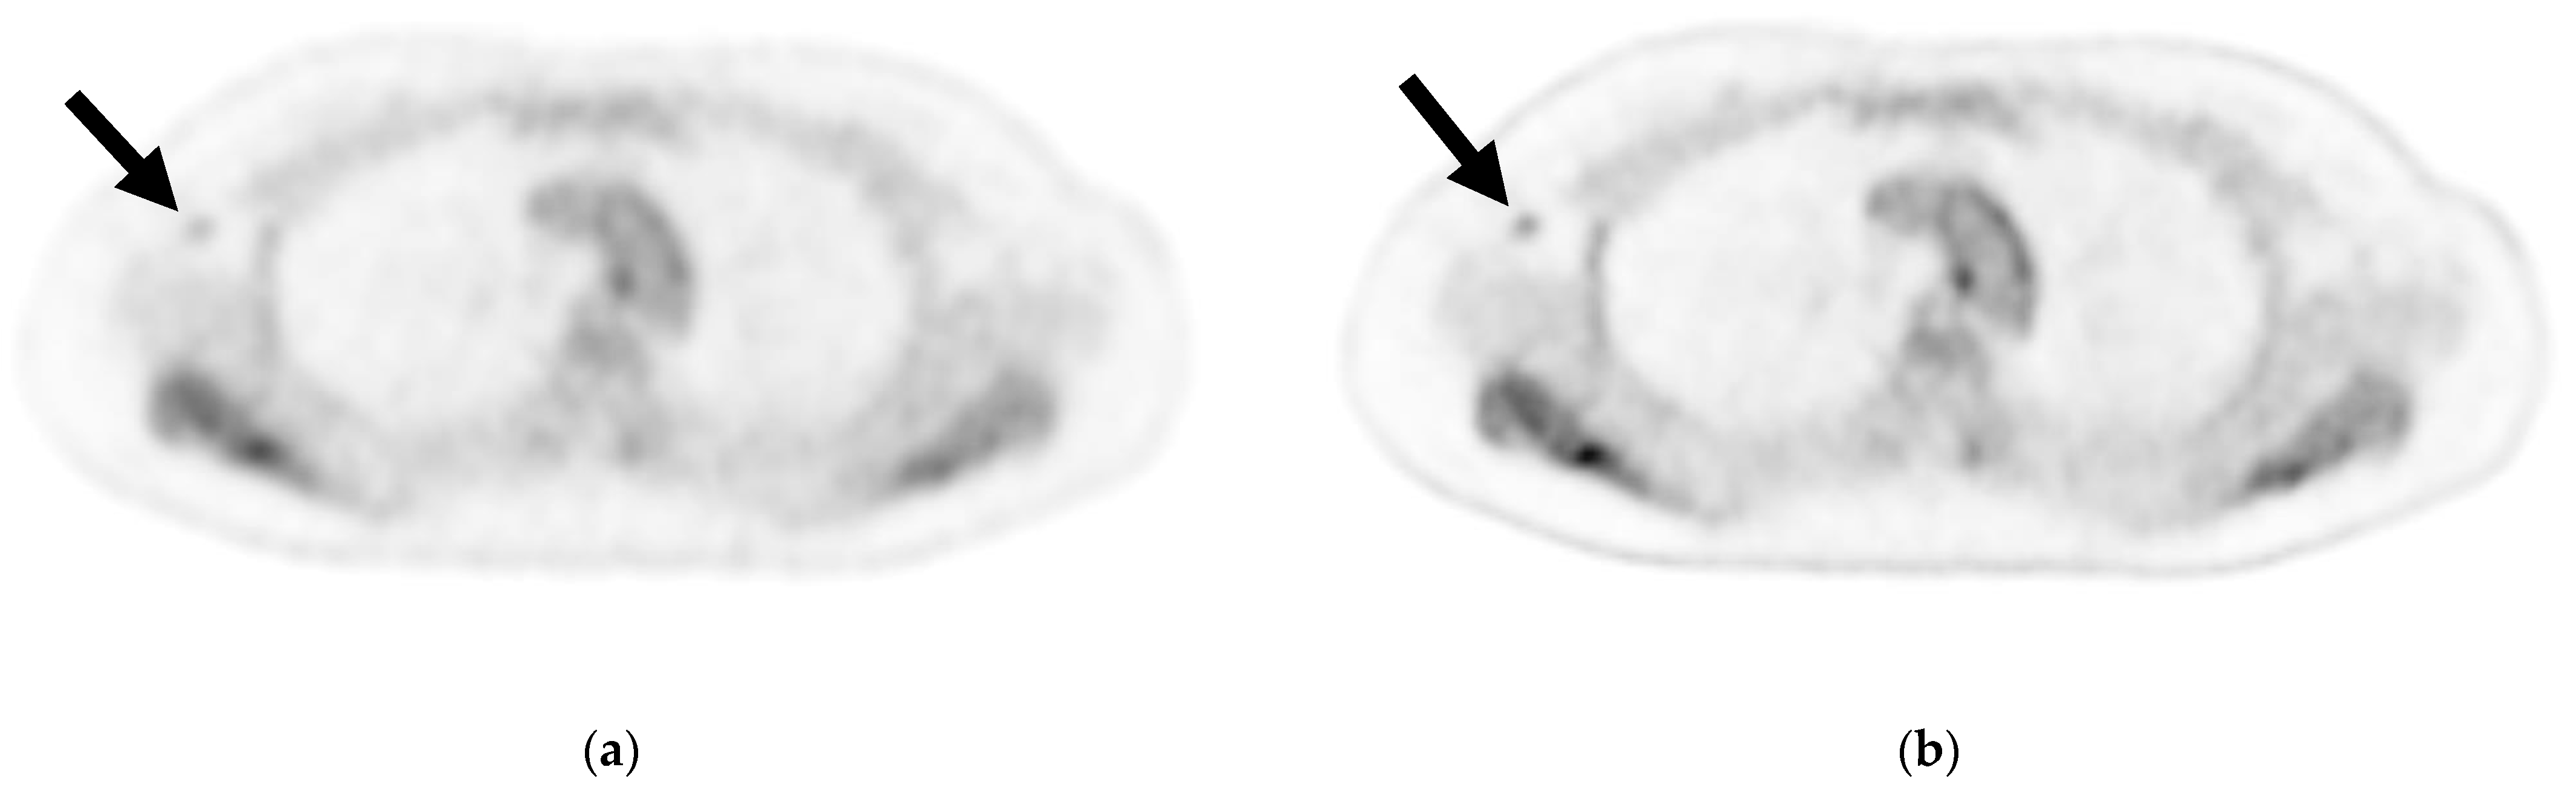

Figure 2.

Axial image of an axillary lymph node (ALN) cross-section via (a) cPET and (b) DL-PET of a woman in her 40 s with invasive lobular carcinoma in the right breast: invasive diameter, 18 mm; nuclear grade, 1; lymphatic invasion, positive; vascular invasion, positive; estrogen receptor, positive; progesterone receptor, positive; HER2 receptor, negative; Ki-67 staining, 17.3%; and nodal stage, 1a. Of 18 ALNs, 3 were positive for metastasis; the maximum diameter was 3 mm, and an extranodal invasion was evident. Visual analysis for ipsilateral ALN metastasis was rated on a scale of 1–3 (1 = negative, 2 = intermediate, 3 = positive). For ALN metastasis, reader 1 gave a score of 2 for cPET and 3 for DL-PET, and reader 2 gave a score of 1 for both the PET types. cPET, PET with conventional reconstruction; DL-PET, PET with deep learning restoration.

Although the contrast between the background axillary adipose tissue and ALNs improved, it did not improve the diagnosis of ALN metastases while using DL-PET (Figure 2). The DL-PET images in metastasis-negative cases were scored 2 or 3 by reader 1 more frequently compared with cPET images. It was difficult to determine whether the 18F-FDG accumulation on DL-PET was associated with metastasis because the accumulation was clear regardless of the presence or absence of ALN metastasis. When scores of 1 and 2 were defined as negative and a score of 3 as positive, both readers reached the same visual diagnosis with cPET reconstructions and DL-PET restorations. When evaluating high-contrast images, such as those obtained using DL-PET, moderate accumulation requires careful assessment to ensure it is not mistakenly labeled as positive for metastasis. In this study, cPET, which was considered as the baseline, was performed using the latest digital PET scanner technology. Hence, it is possible that the image quality was too good to demonstrate a significant difference between cPET and DL-PET.